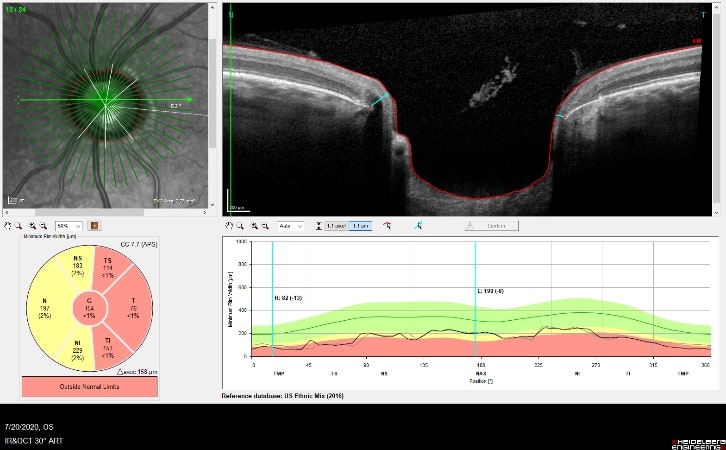

OCT is used in glaucoma to image the optic nerve and the nerve fiber layer in order to determine if there is damage from increased eye pressure. Because the resolution of OCT is so high, it can detect fine changes to the shape of optic nerve. Thinning of the nerve fiber layer is a sign that glaucoma is worsening and that the eye pressure is too high.

OCT Imaging showing a

Cupped Optic Nerve

Structural changes to the optic nerve or nerve fiber layer usually precede visual field loss. In many cases, 50% of the optic nerve can be damaged before visual field loss develops. As a result, OCT is a critical tool for diagnosing glaucoma at its earliest stages.

An example of an optic nerve with glaucoma damage imaged with both fundus photography and OCT and compared to the visual field in order to demonstrate the strucure-function relationship.

The lower half of the optc nerve has early damage, and this correlates with the small superior scotoma seen on the visual field test.